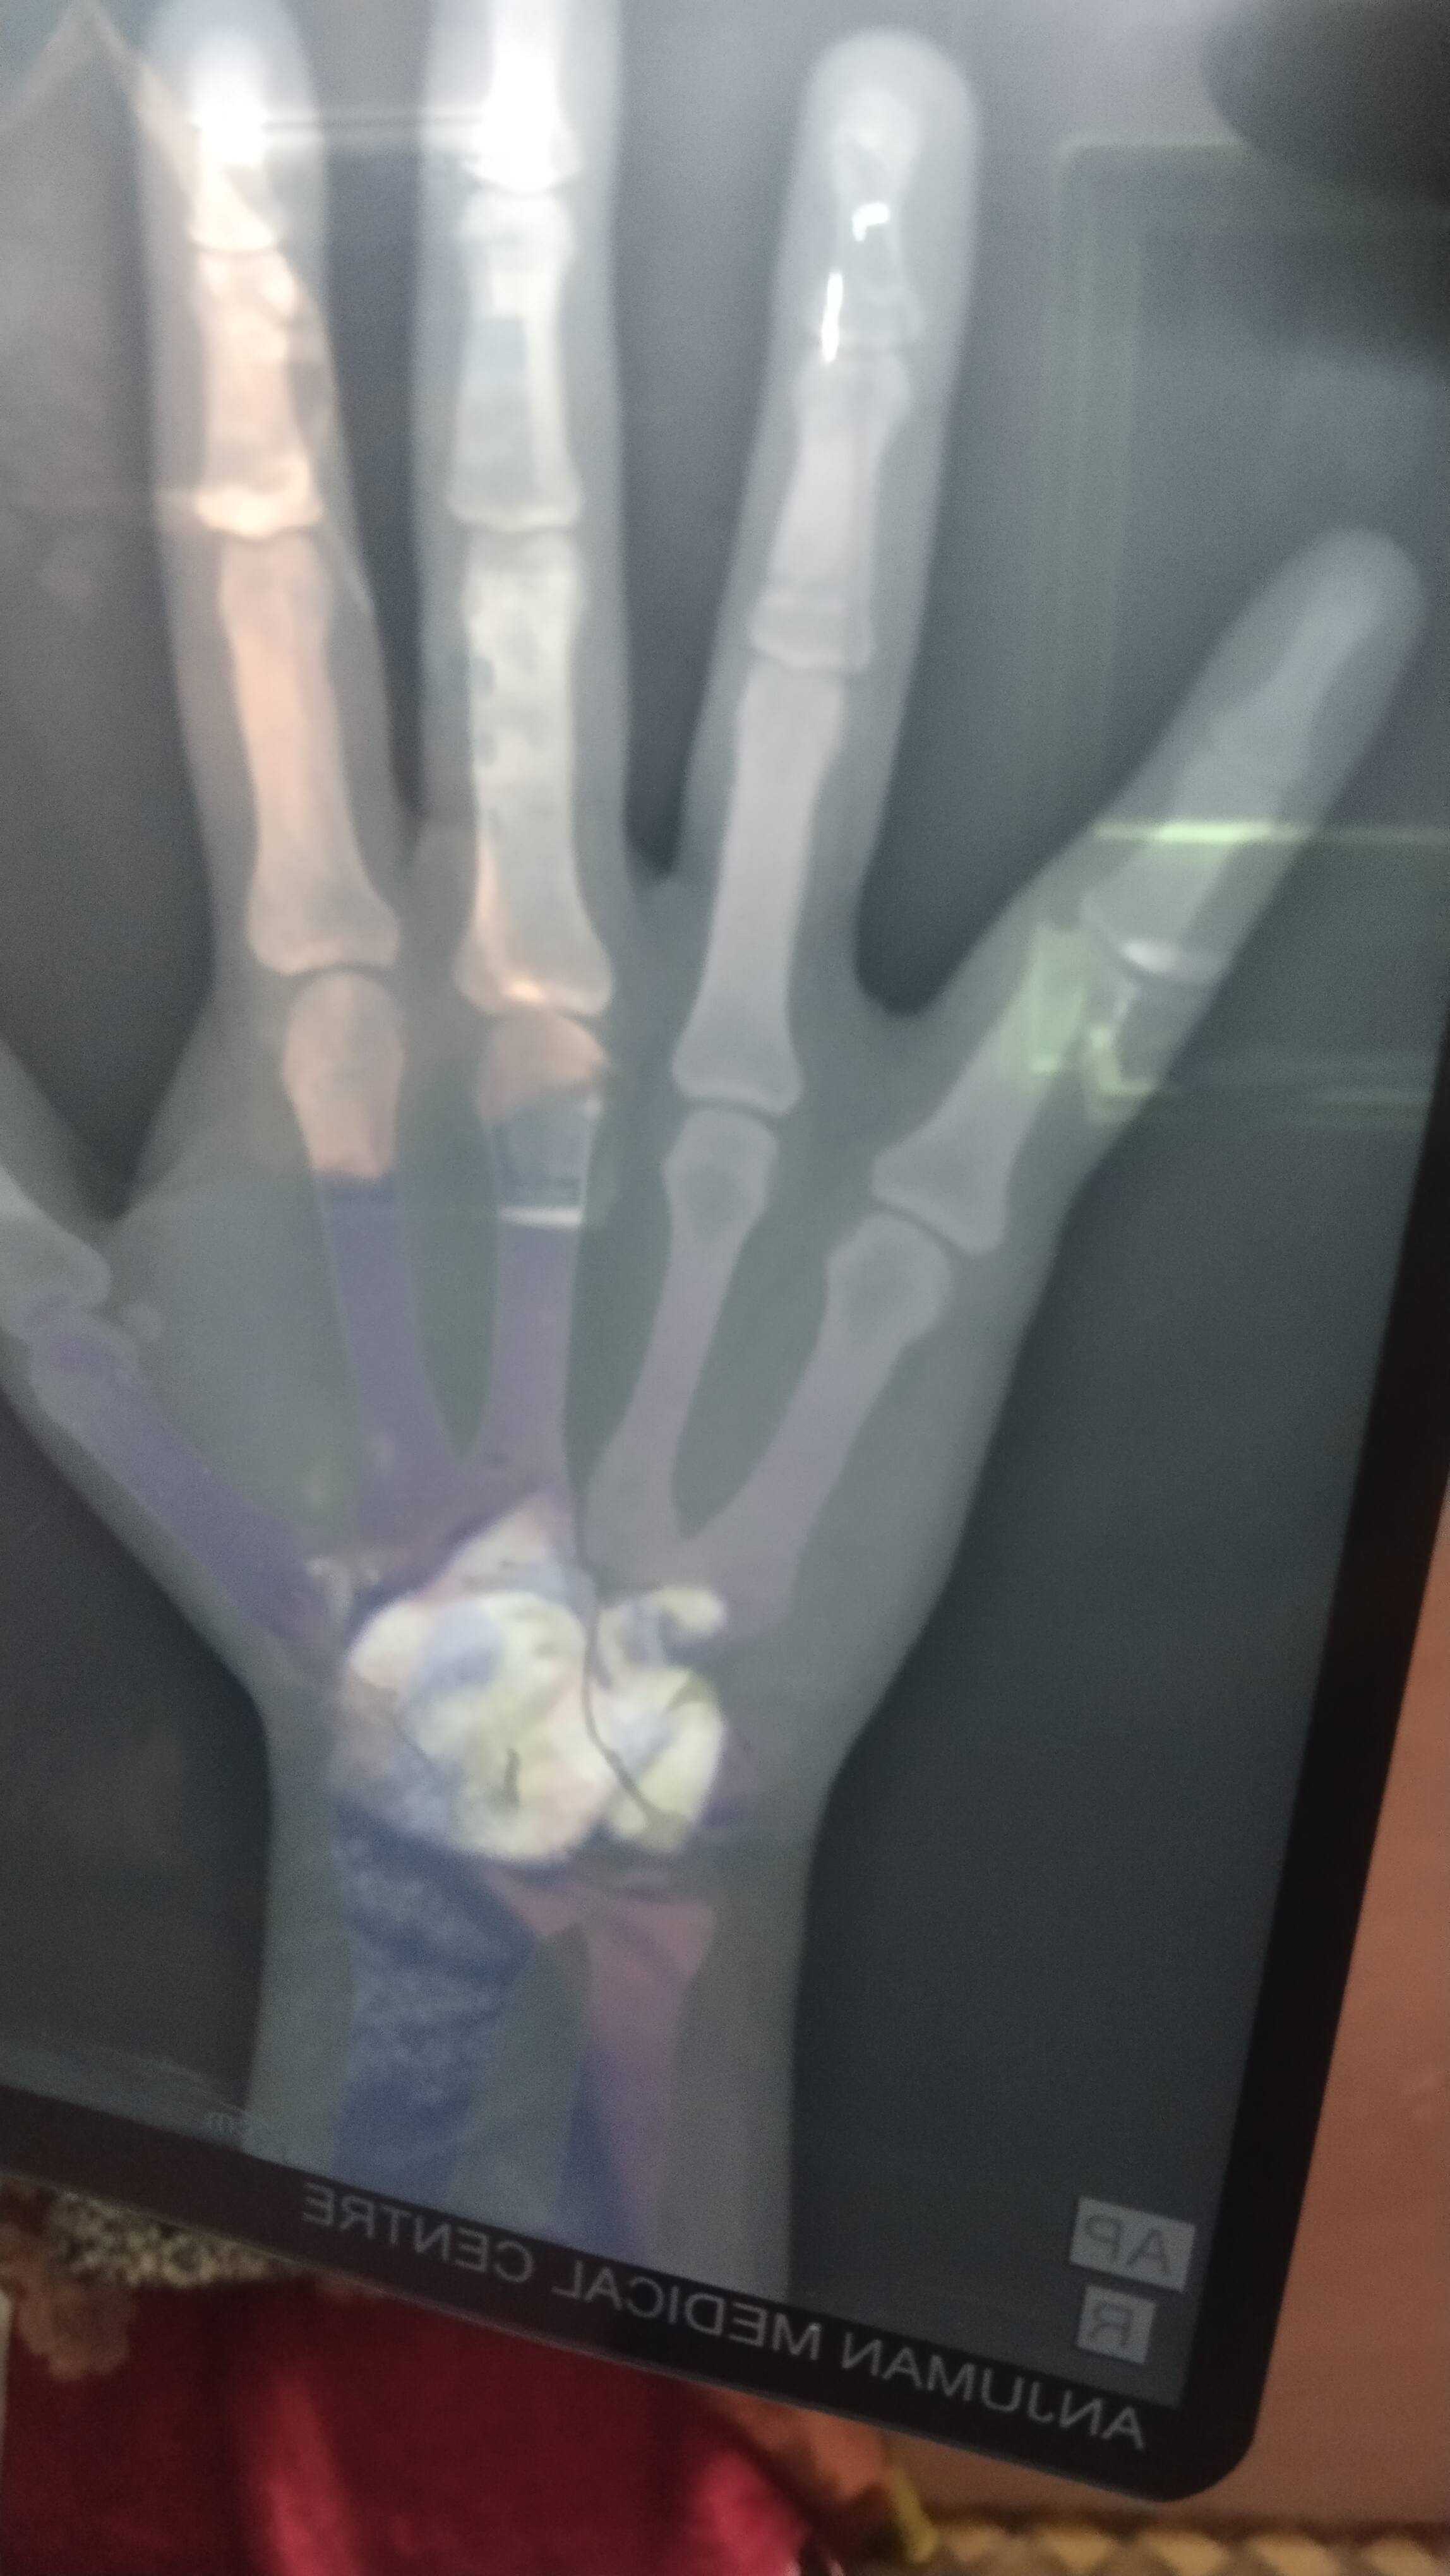

What is preferable plaster here, plaster,k-wire or plate

Little finger me fracture hai right hand ki

Sir क्या यह प्लास्टर द्वारा ठीक होगा या ऑपरेशन द्वारा नेल डालना होगा दोनो मैं कितना टाइम लगेगा रिकवरी मैं उमर 29 साल है पहले जैसा होने में टाइम लगेगा